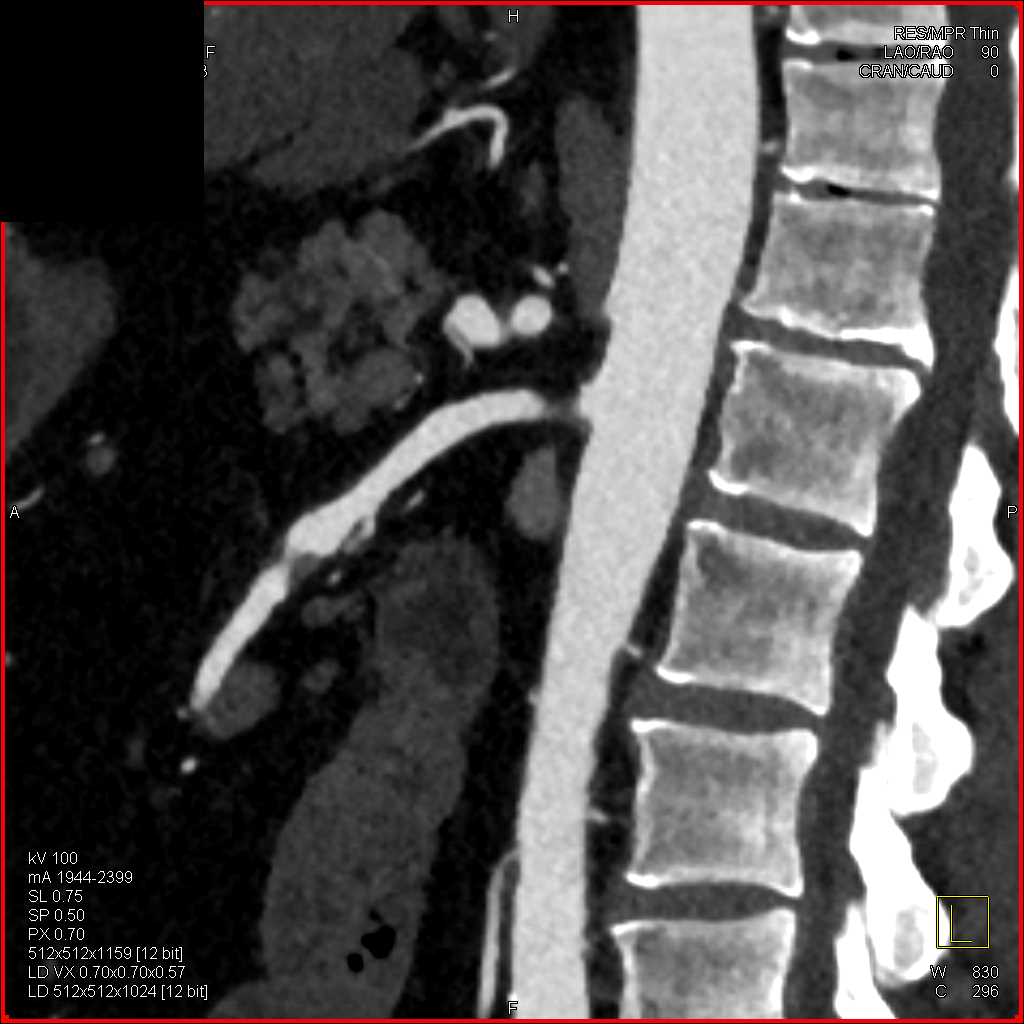

SMA Stenosis